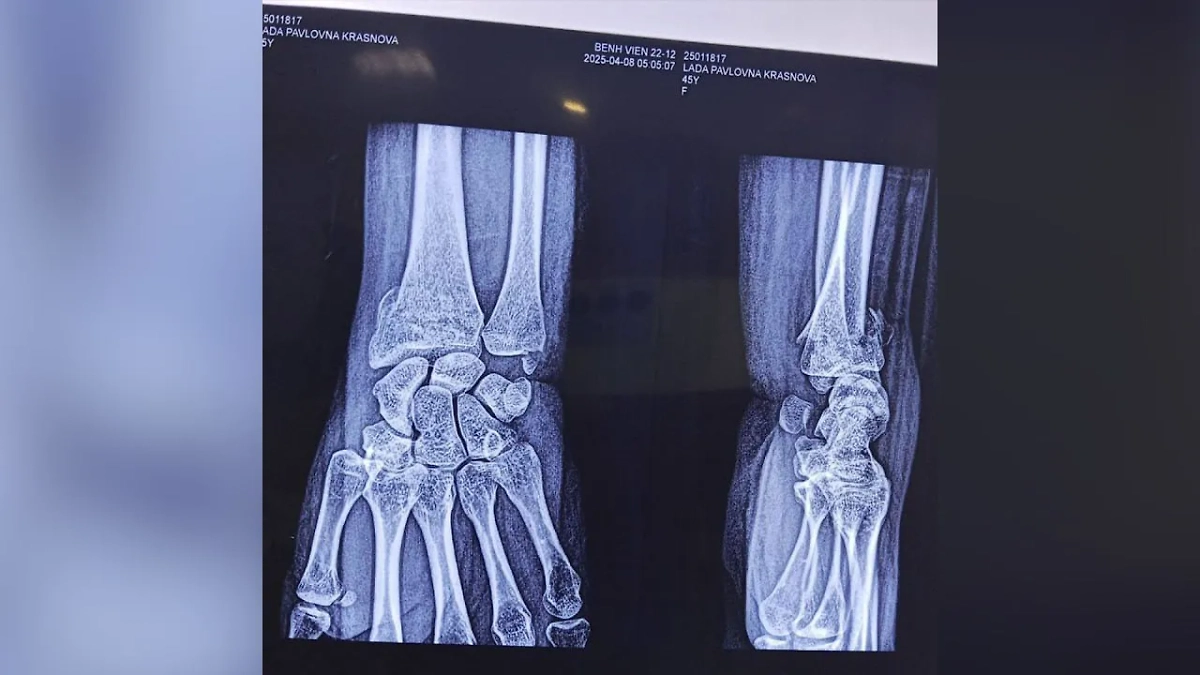

Результат оказался чудовищным: сломанная в трёх местах рука и огромная гематома, из-за которой девушка не может спать и лежать на спине. также у россиянки много ссадин и ушибов по всему телу. Нападавший после избиения скрылся с места происшествия. Сейчас его разыскивает полиция.

У россиянки перелом руки в трёх местах. Фото © SHOT